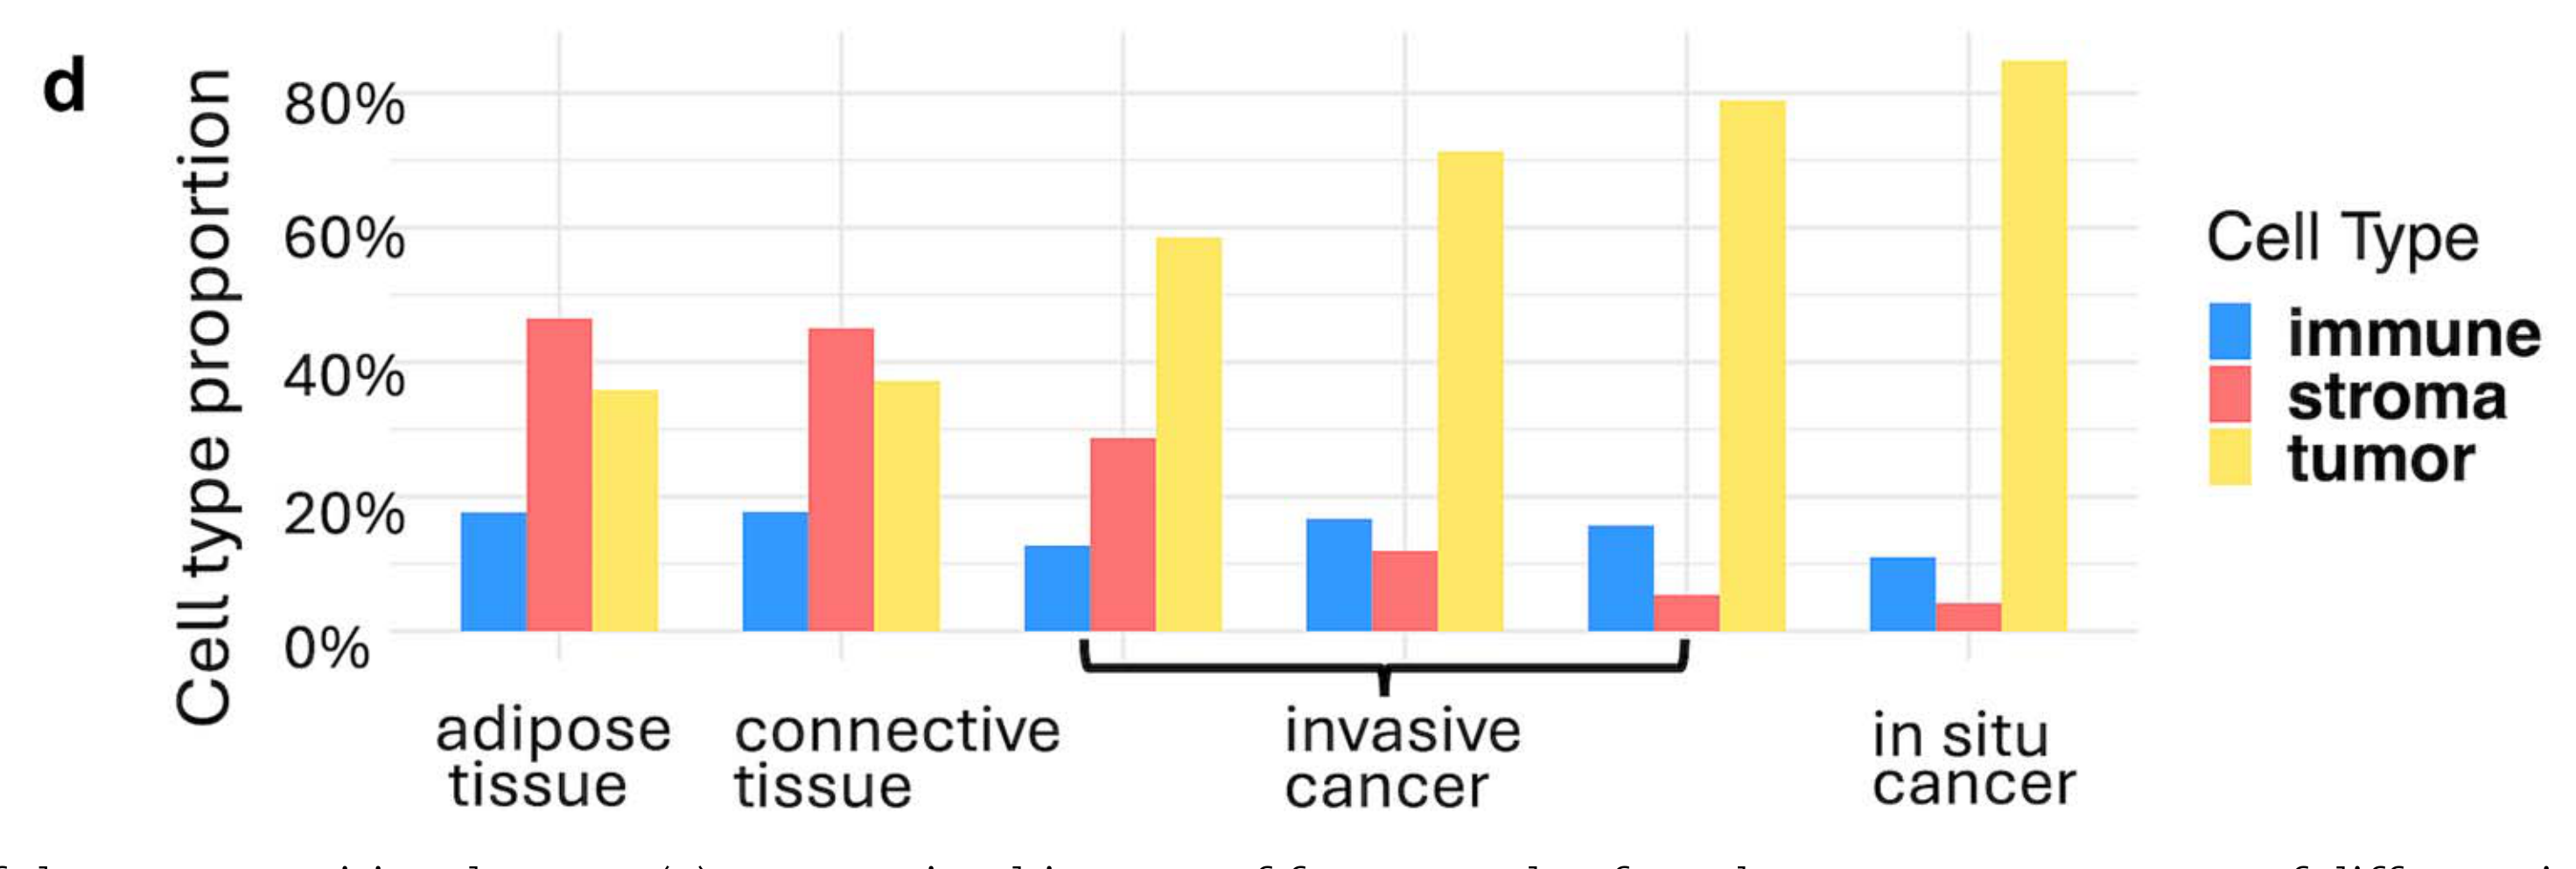

How does the cellular composition of a tissue vary across spatially defined domains?

Biological

Cellular

Abstraction

Complete

Chart Type

Bar plot

Communicative/Contextualization

Highlighting

Comparative Design

Juxtaposition

Layout

Linear

Scalability Strategy

Summay/Aggregate